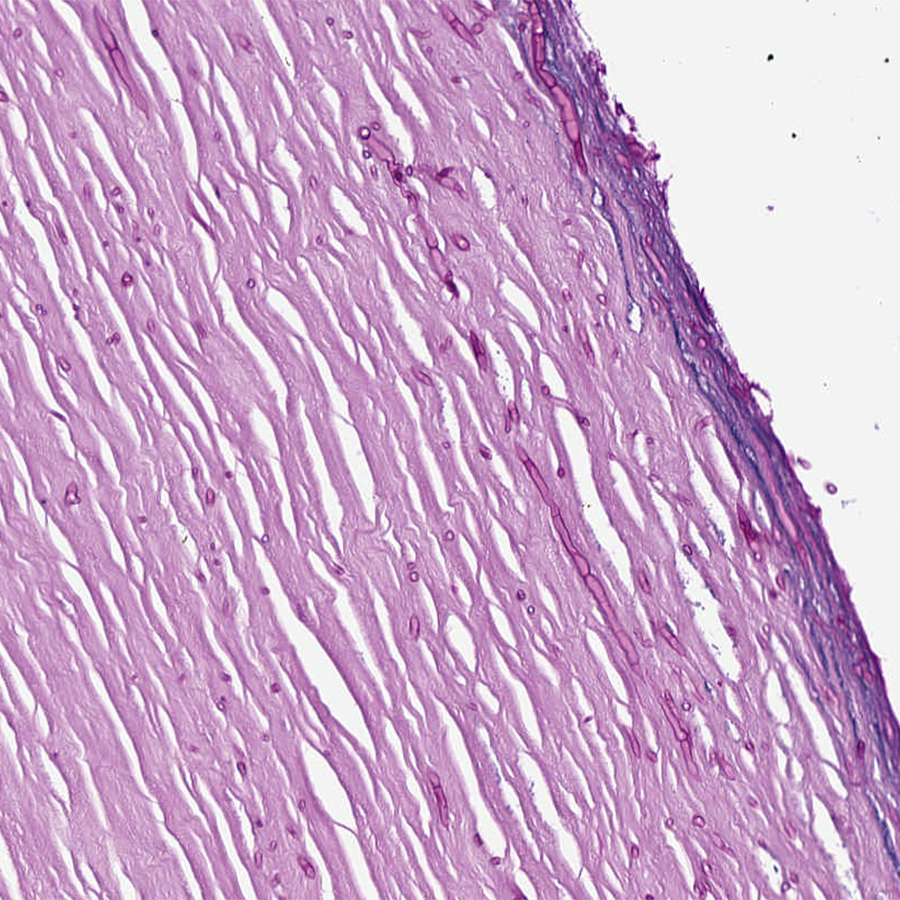

Histology of calcified

#Retinoblastoma (post treatment). A#FlexnerWintersteiner rosette in the last pic#pedipath#eyepath pic.twitter.com/knJ7OacgRT